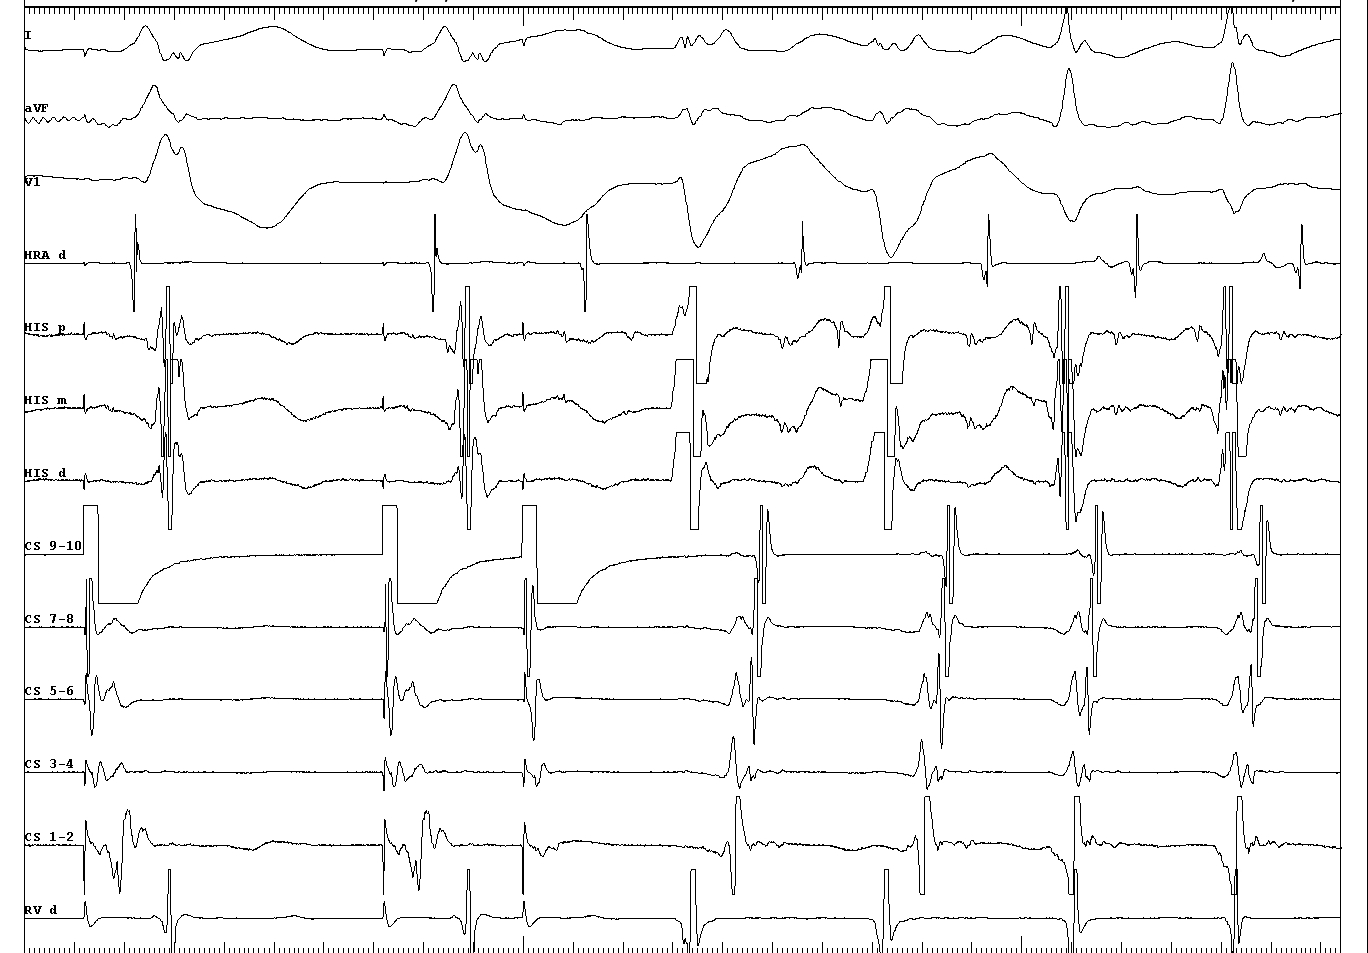

Termination during VOP - What now ?

vop_termination.jpg

Onset of VOP

vop_onset.jpg

Middle of VOP

02_constant and progressive fusion.JPG

Entrainment with antegrade His

entrain_with_fusion.jpg

Termination during VOP

termination_with_fusion.JPG